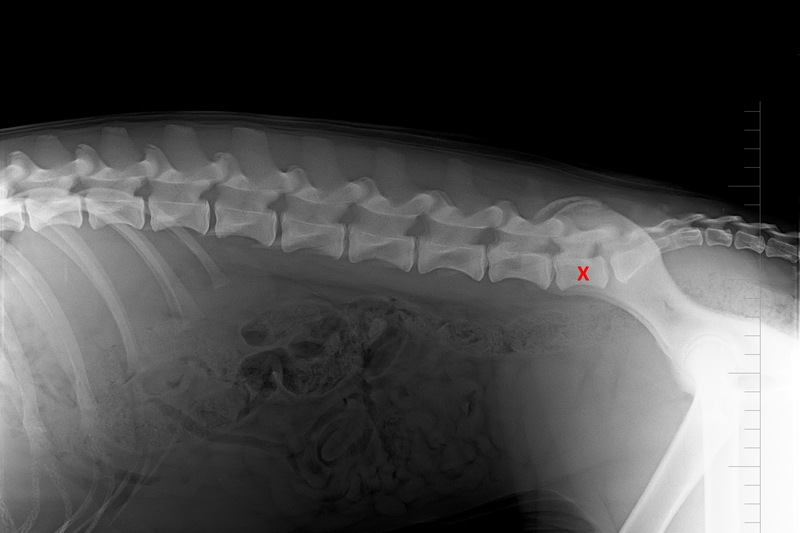

Diagnostika přechodového obratle je založena na rentgenologickém vyšetření. Přechodový obratel bývá poprvé diagnostikován ještě v době, kdy nepůsobí žádné potíže, a to jako náhodný nález při rutinní diagnostice dysplazie kyčelních kloubů v takzvané ventrodorsální projekci, kdy pes leží na zádech s pánevními končetinami nataženými dozadu.

Ke zjištění počtu bederních obratlů bývá jako upřesňující využívána laterolaterální projekce, kdy pes leží na boku. Na naší klinice k upřesnění diagnózy dále provádíme RTG vyšetření bederní páteře a kosti křížové ve ventrodorsální projekci, jež nám umožnilo v několika případech diagnostikovat i thorakolumbální přechodový obratel (lokalizovaný na přechodu hrudní a bederní páteře) a také tzv. laterální spondylózu.

(2) 7 týdnů lat

(2) typ 3 I

(5) 7 měsíců lat

(5) typ 3 páteř VD

páteř LL